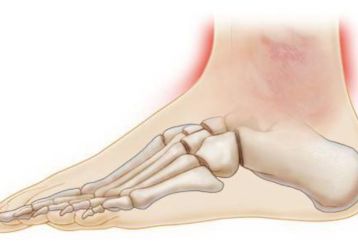

Ушиб голеностопного сустава: основные признаки, первая помощь, тактика лечения

Что такое ушиб голеностопного сустава, как его определить. Меры первой помощи, способы лечения медикаментами, физпроцедурами, народными средствами.